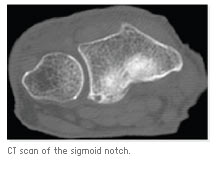

Fifteen freshly frozen, unpaired mid-brachium hand specimens were used. CT Scans were taken, followed by dissection and reconstruction of the distal radius. The sigmoid notch surface is divided into two surfaces - the articulating, an average of 79.78 mm2 (69.13%); and the non-articulating, an average of 35.84 mm2 (30.87%). The Anterior Posterior (AP) and Proximal Distal ((PD) widths of the articulating surface and the PD width of the sigmoid notch were reviewed, along with the radius of curvature, version angle and depth of the sigmoid notch.

The inclination of the sigmoid notch towards the radial axis was visible at 1.64 degrees with ranges between - 14.46 degrees to +11.34 degrees. The AP width of the distal radius was 12.9 mm, the PD width of the articulating surface was 5.1 mm and the PD width of the sigmoid notch was 8.1 mm. The radius of curvature of the sigmoid notch was 14.6 mm, and the version angle was 9.8 degrees. The maximum depth of the sigmoid notch was 1.67 mm.

Our measurements of the AP width and radius of curvature of the sigmoid notch were compatible to previous studies. We defined the version angle and maximum depth of the sigmoid notch. We defined the proximal border of the DRUJ and the articular surface. The study showed that the sigmoid notch is flatter than previously believed. Only the distal 69% of its surface is covered by cartilage. On average, the sigmoid notch has about 9 degrees of retroversion and its average inclination is almost parallel to the anatomical axis of the radius. Clinical implications exist for evaluation of the DRUJ involvement in distal radius fractures or degenerative diseases - and in the future development and evaluation of hemiarthroplasty replacement of the distal radius.